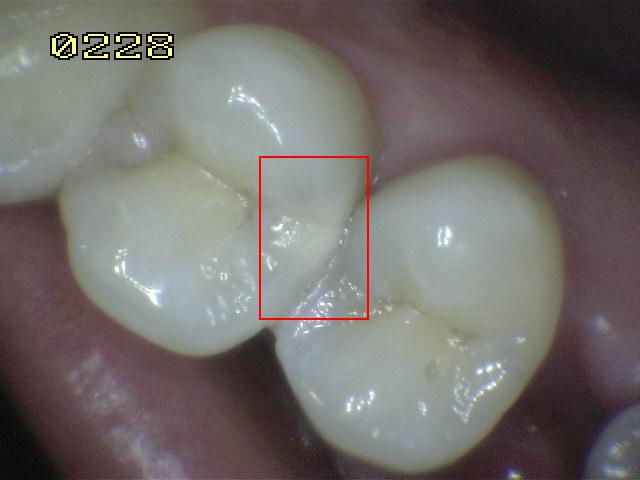

Código 2

(Caries Inicial): Lesión de

caries observada en esmalte en estado húmedo y permanece después de

secar.

- La lesión puede verse directamente desde vestibular,

lingual o palatino.

Mancha blanca / marrón consistente con

desmineralización de esmalte.